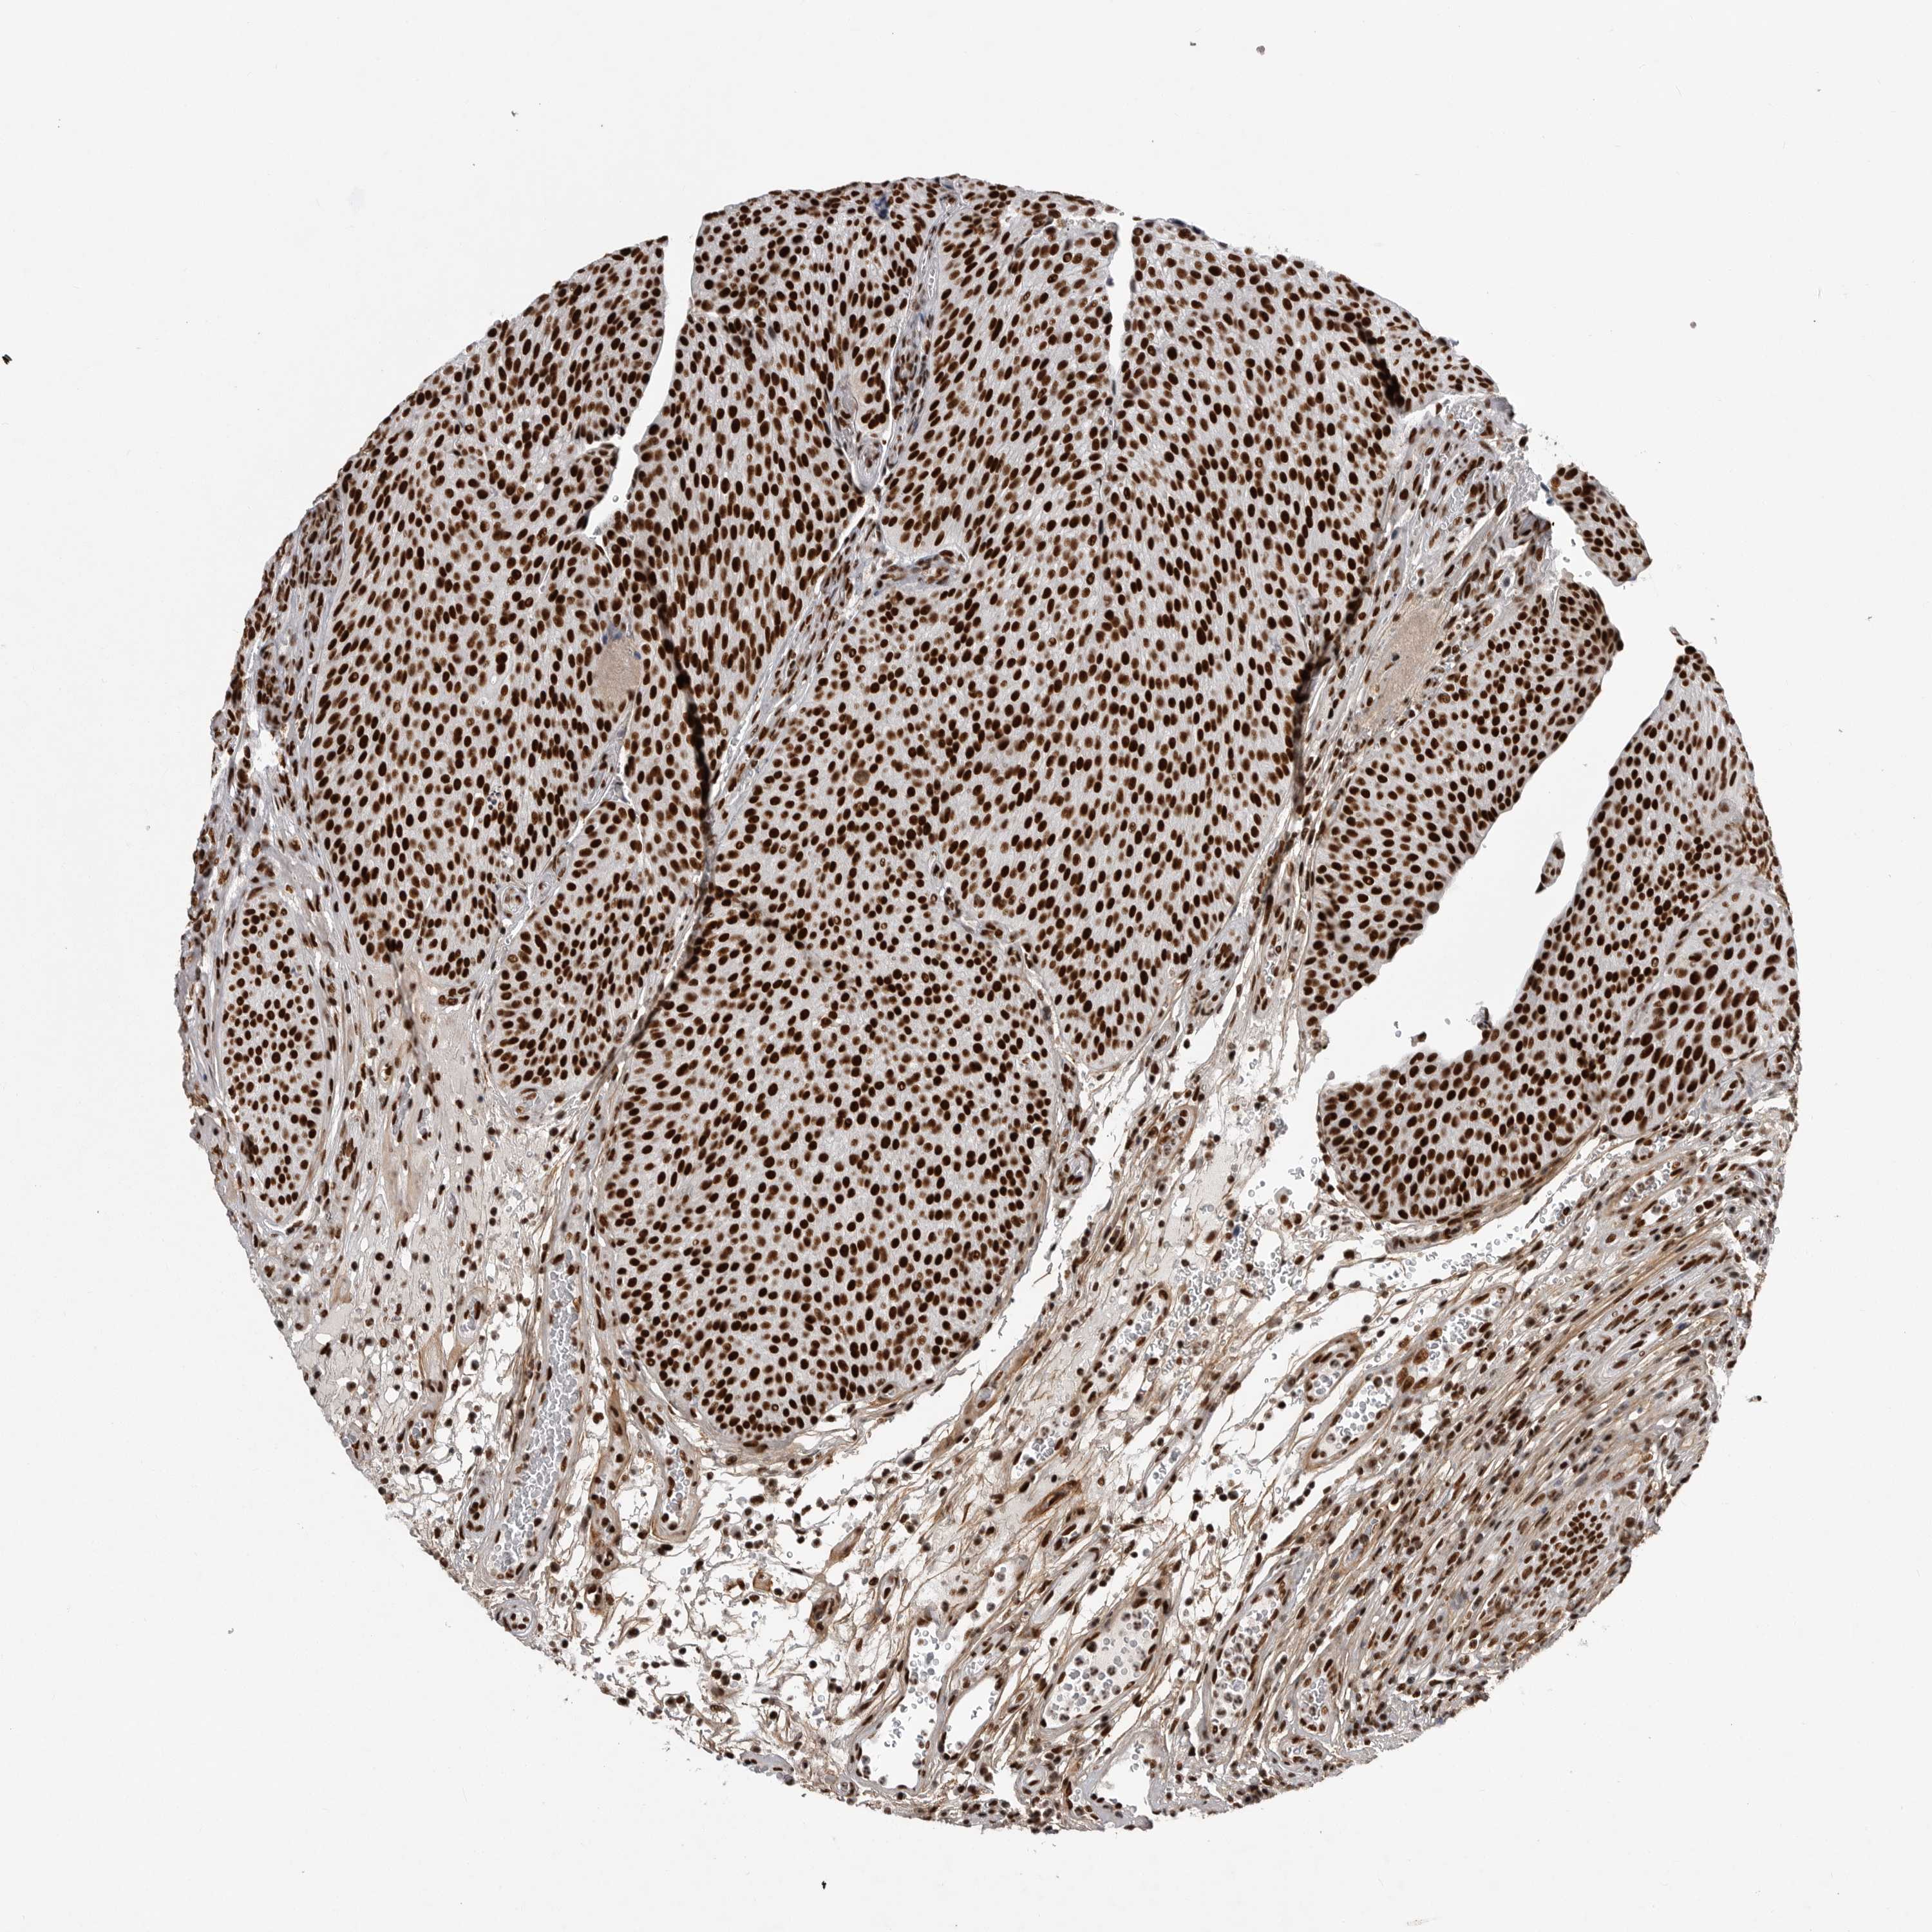

UROTHELIAL CANCER - Protein expressioni

A mouse-over function shows sample information and annotation data. Click on an image to view it in a full screen mode. Samples can be filtered based on level of antibody staining by selecting one or several of the following categories: high, medium, low and not detected. The assay and annotation is described here.

Note that samples used for immunohistochemistry by the Human Protein Atlas do not correspond to samples in the TCGA dataset.

Antibody stainingi

Antibody staining in the annotated cell types in the current human tissue is reported as not detected, low, medium, or high, based on conventional immunohistochemistry profiling in selected tissues. This score is based on the combination of the staining intensity and fraction of stained cells.

Each image is clickable and will lead to virtual microscopy that enables deeper exploration of all samples and also displays staining intensity scores, fraction scores and subcellular localization as well as patient and tissue information for each sample.

Antibody HPA027406

Antibody HPA027417

Antibody HPA027452

Staining

High

Medium

Low

Not detected

Intensity

Strong

Moderate

Weak

Negative

Quantity

>75%

75%-25%

<25%

None

Location

Nuclear

Cytoplasmic/membranous

Cytoplasmic/membranous,nuclear

Urothelial carcinoma, Low grade

Urothelial carcinoma, High grade